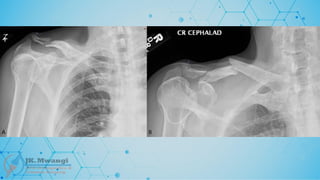

CLASSIFICATION

• Bone = 3

• Segment = 3

• Type = C

• Group = 3

• 33-c3

• Segment = 2

• Type = A

• 32-A3